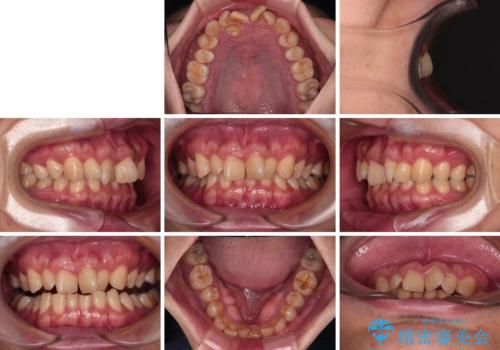

- 前歯のデコボコと深い咬み合わせを気にして来院された患者様です。

骨格的に上顎骨がやや前方にあり、それが原因で下顎前歯が隠れるほどのディープバイトになっている状態でした。

補助装置を用いて、上顎大臼歯を積極的に後方移動させながら、ディープバイトを改善していくこととしました。

強い咬合力に抵抗するため、上下ともに表側のワイヤー装置にて矯正治療を行うこととしました。